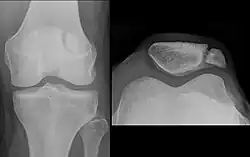

The patella can break in various ways depending on the way it is injured, and into two or more pieces.[1] Types include transverse, the most common, with one fracture line;[5] marginal; osteochondral; and the rare vertical type, or stellate, where a direct compression force gives rise to a comminuted pattern.[5][7] Patella fractures can be further classified as displaced, where the broken ends of bone do not line up correctly and separate by more than 2mm, or undisplaced and stable where pieces of bone remain in contact with each other.[1][7] If fragments of patella bone stick out from the skin it is known as an open patella fracture, and closed if the overlying skin is intact.[1]

-

Transverse fracture of patella -

Comminuted fracture of patella -

Osteochondral fracture of patella -

Vertical patella fracture